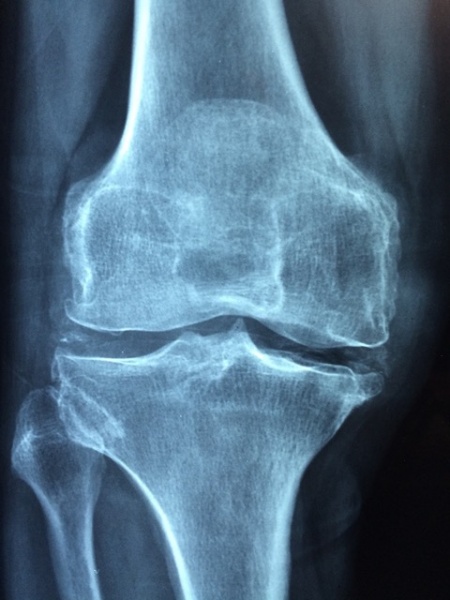

Staw kolanowy jest największym stawem w ciele człowieka. Łączy kość udową i kość piszczelową. Ze względu na duże obciążenie ze strony kości udowej, potężną siłę mięśnia czworogłowego uda oraz wykonywanie niekorzystnych dla niego rotacji, jest stawem najbardziej podatnym na obciążenia i urazy. Nauczyciele jogi kładą wobec tego duży nacisk na jego bezpieczeństwo podczas praktyki.